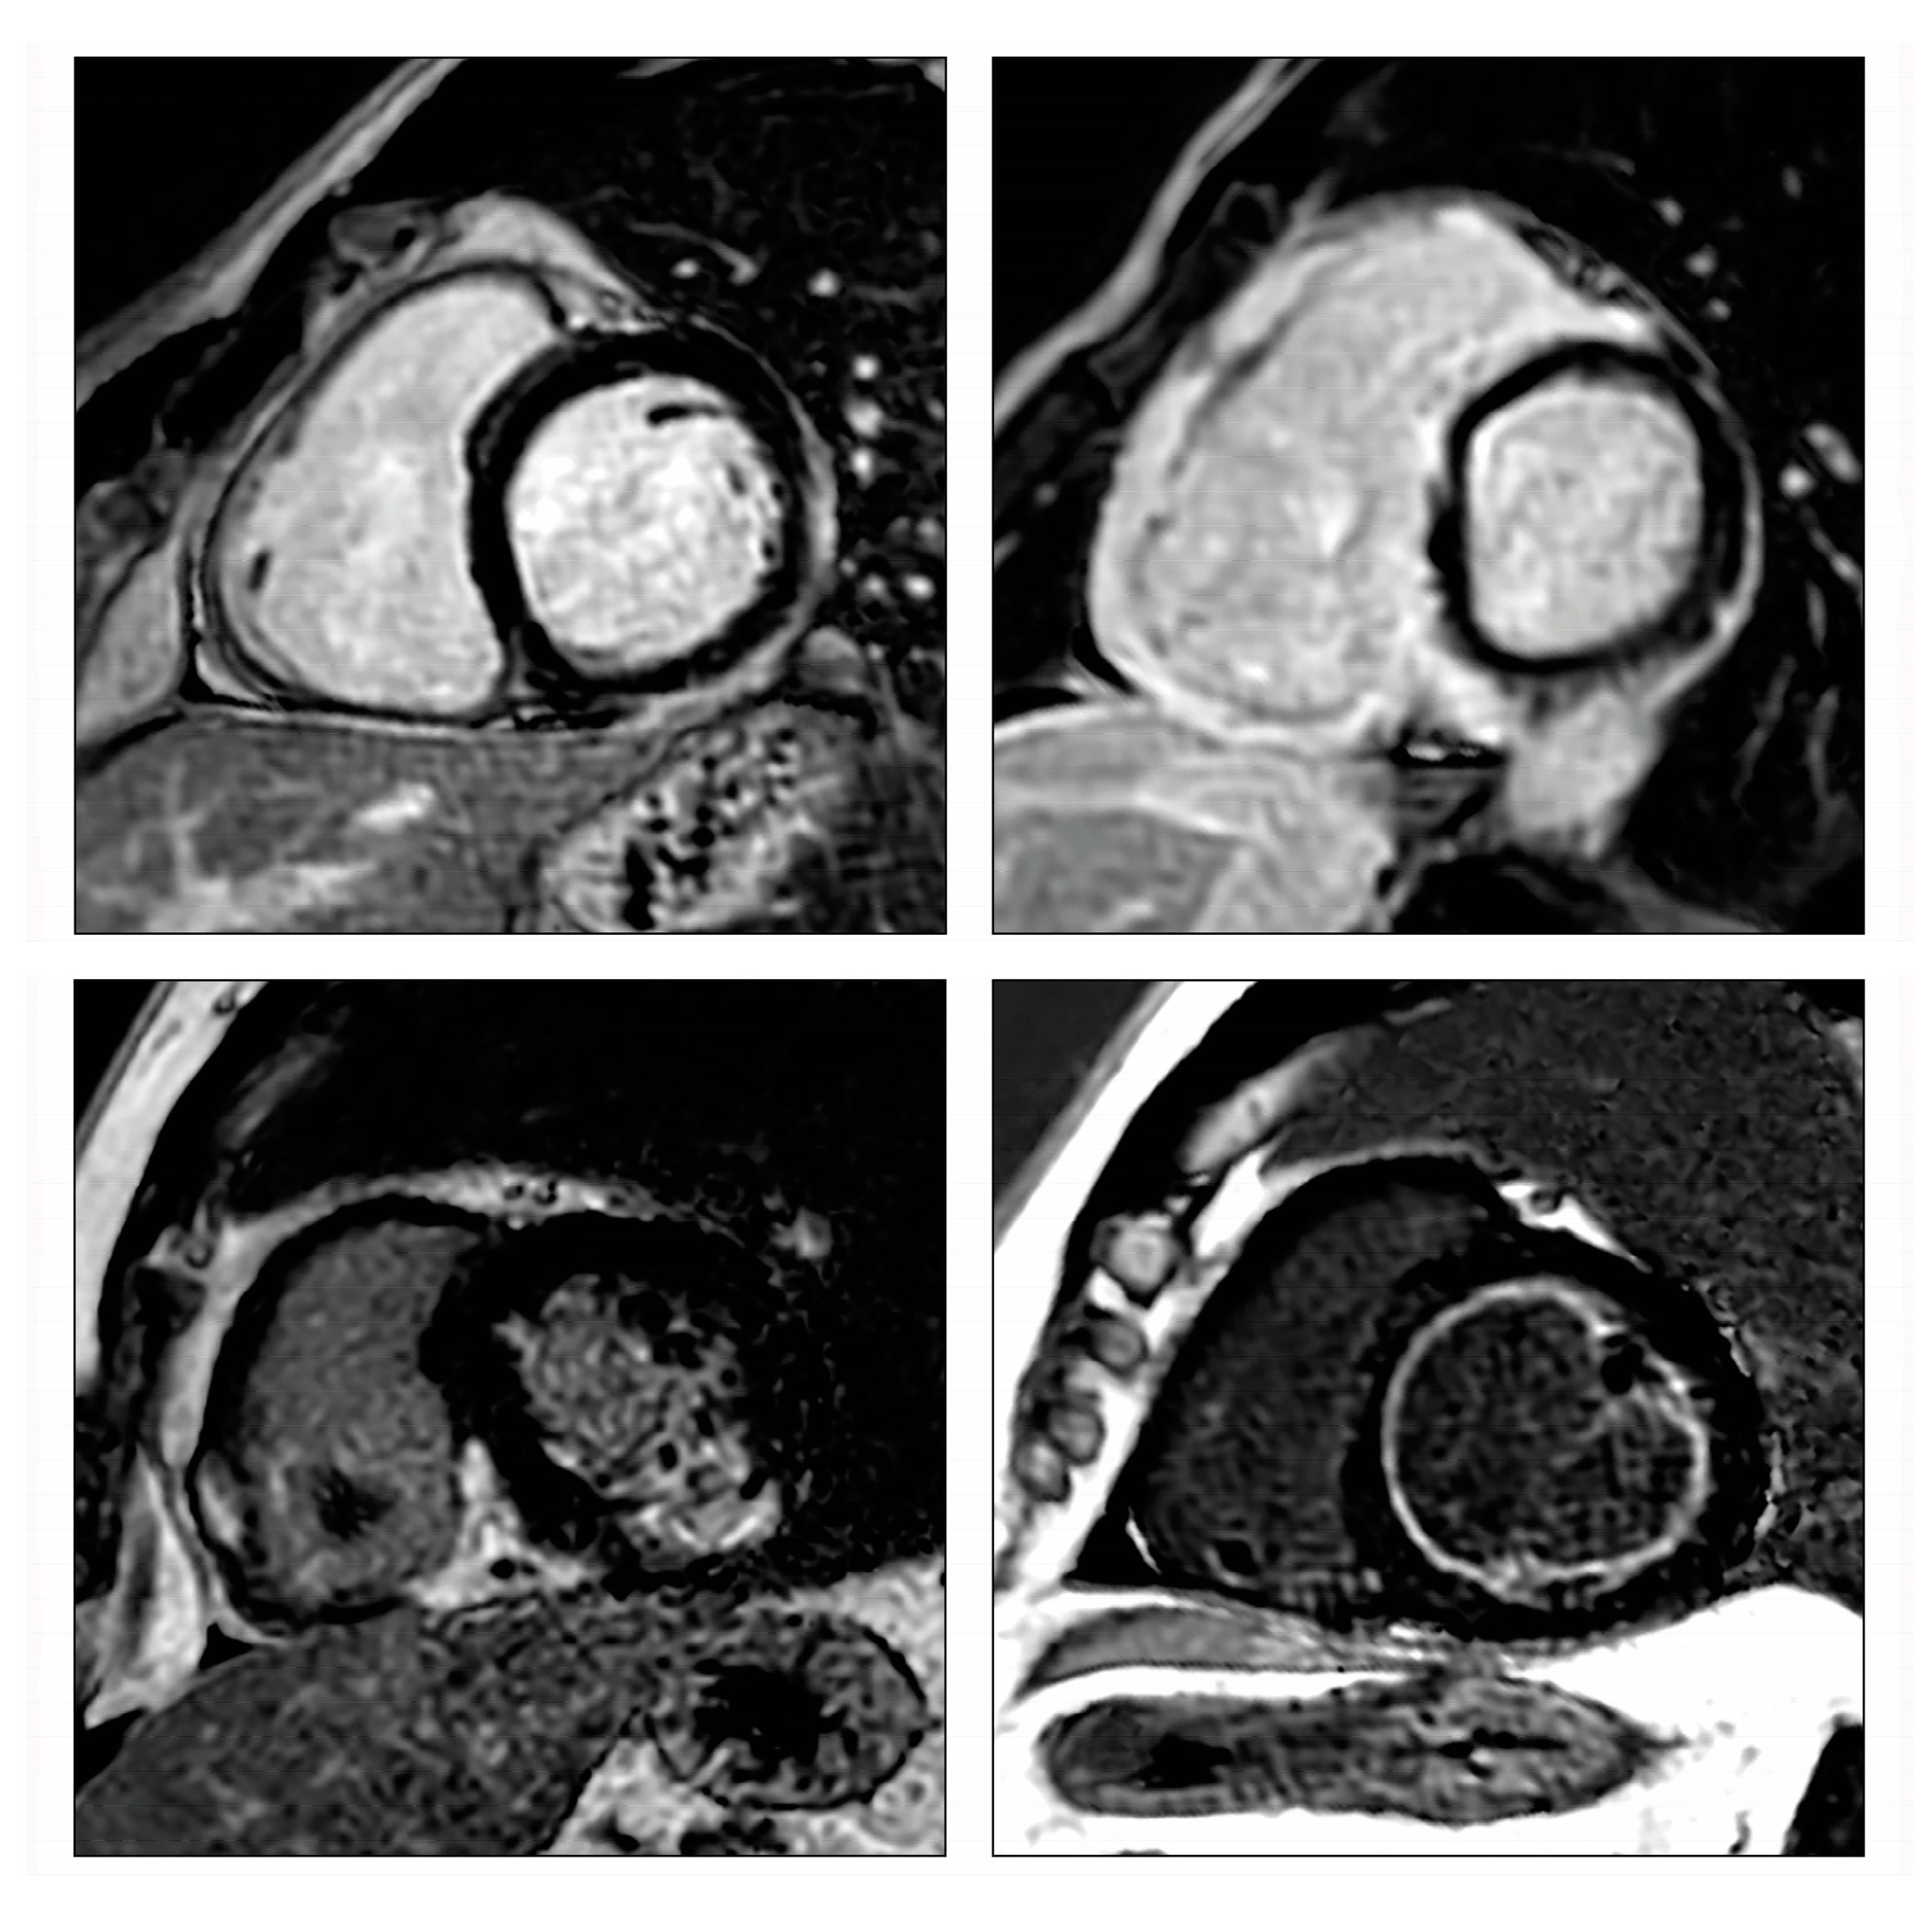

- Poyhonen, P.; Nordenswan, H.K.; Lehtonen, J.; Syvaranta, S.; Shenoy, C.; Kupari, M. Cardiac magnetic resonance in giant cell myocarditis: A matched comparison with cardiac sarcoidosis. Eur. Heart J. Cardiovasc. Imaging 2023, 24, 404–412. [Google Scholar] [CrossRef]

- Bobbio, E.; Bollano, E.; Oldfors, A.; Hedner, H.; Björkenstam, M.; Svedlund, S.; Karason, K.; Bergh, N.; Polte, C.L. Phenotyping of giant cell myocarditis versus cardiac sarcoidosis using cardiovascular magnetic resonance. Int. J. Cardiol. 2023, 387, 131143. [Google Scholar] [CrossRef]